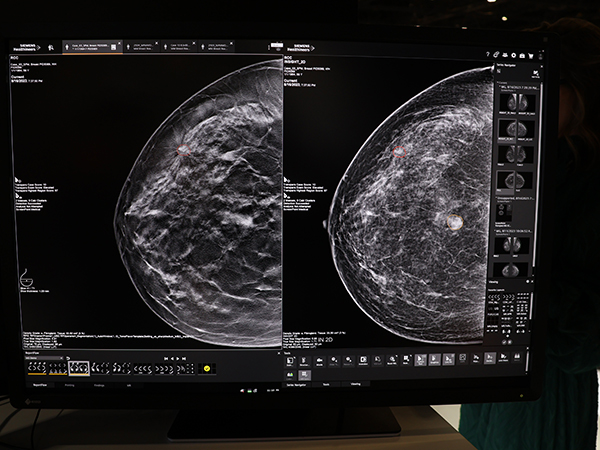

また,人工知能(AI)の展開として,グローバルではSiemens HealthineersのマンモビューワにScreenPoint社のCADである「Transpara Breast AI」を搭載した(薬機法未承認)。病変が疑われる箇所を丸で囲み,悪性度が最も高いものは赤,悪性度が中等度のものは黄色の線で表現するなど,正確かつ効率的な診断を支援している。

マンモビューワにScreenPoint社のCAD「Transpara Breast AI」を搭載し,正確かつ効率的な診断を支援